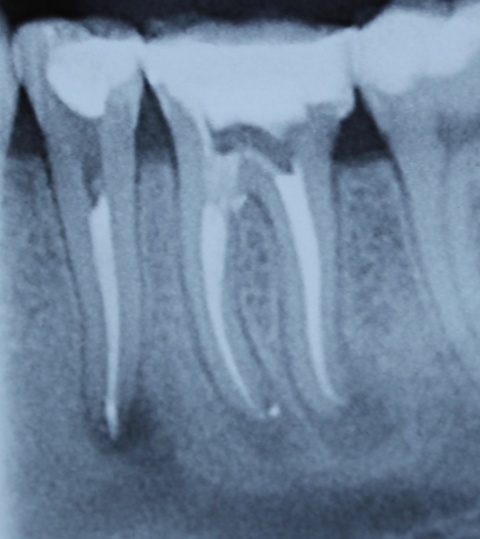

Durch eine Vielzahl von Studien konnte belegt werden, dass die Versorgung mit implantatgetragenem Zahnersatz eine bewährte Behandlungsoption darstellt. Gleichwohl zeigen viele Studien jedoch, dass – wie bei allen Therapiemaßnahmen auch – Komplikationen auftreten können. Diese haben im Allgemeinen biologische oder technische Ursachen. Als häufigste biologische Komplikation findet man die Mucositis (Abb. 1), die Entzündung der periimplantären Gewebe ohne Beteiligung des Alveolarknochens. Nach aktuellen Studien weisen ca. 30 % aller Implantate nach fünf Jahren eine Mucositis auf. Kommt es darüber hinaus zu einer Beteiligung des Alveolarknochens, liegt eine Periimplantitis vor (Abb. 2). Sie tritt nach fünf Jahren bei etwa 10 % der inkorporierten Implantate auf und ist durch den Verlust des periimplantären Alveolarknochens gekennzeichnet. Die Periimplantitis kann, je nach Schweregrad, zum kompletten Implantatverlust führen. Bei einem strategisch wichtigen Implantat kann daraus der Verlust der gesamten prothetischen Versorgung resultieren und eine operativ sowie finanziell aufwendige Neuversorgung erforderlich werden (Abb. 3).

Ziel ist es, durch die Entfernung von Gewebs- und/oder Zahnanteilen die Zugänglichkeit zu schwer zugänglichen parodontalen Defekten zu verbessern. Darüber hinaus kann durch diese Maßnahmen die Hygienefähigkeit verbessert und eine Neubesiedelung des Parodontiums durch die mikrobielle Plaque verhindert werden. Vor allem die Prognose von furkationsbeteiligten Molaren kann auf diese Weise deutlich verbessert werden. In einer vielbeachteten Studie aus dem Jahre 2001 haben Fugazotto und Mitarbeiter die Prognose von 701 resektiv behandelten Molaren untersucht und beeindruckende Ergebnisse erzielt. Nach 15 Jahren waren noch 678 Molaren (94,9 %) in situ und erfüllten die vorgegebenen Erfolgskriterien. So lautete dann auch die Kernaussage dieser Studie, dass bei richtiger Indikationsstellung resektiv behandelte Molaren mindestens die gleich gute Langzeitprognose wie Implantate haben. In diesem Zusammenhang sei erwähnt, dass die Voraussetzung für eine erfolgreiche resektive Therapie die erfolgreiche endodontische Behandlung ist. Wie später noch ausgeführt wird, haben sich gerade auf diesem Gebiet durch technische Neuerungen völlig neue Möglichkeiten ergeben, was die Prognose der resektiv behandelten Molaren weiter verbessern dürfte. Ein kleines Beispiel, wie durch derartige Behandlungsschritte eine Implantation verhindert werden kann, zeigen die Abb. 5 und 6, wo durch eine Hemisektion des mesialen Wurzelanteils am Zahn 46 und anschließende Versorgung mit einer kleinen Brücke von 45 auf 46 eine Implantatinkorporation unnötig wurde.

Eine Schnittstelle zu den bereits ausgeführten parodontalen Voraussetzungen des Zahnerhalts ergibt sich bei kombinierten Paro-Endo-Läsionen beziehungsweise Endo-Paro-Läsionen. Zeigen konservative Behandlungsansätze bei den meisten dieser Befunde gute Ergebnisse, ist bei einem lokal ausgeprägten Knochenabbau zumeist die chirurgische Intervention zum Zahnerhalt notwendig (Abb. 11 und 12). Wichtig dabei ist die Unterscheidung der primären Ursache (primär endodontische oder primär parodontale Ätiologie) der Läsion und einem dieser Ursache angepasstem Behandlungsprotokoll.